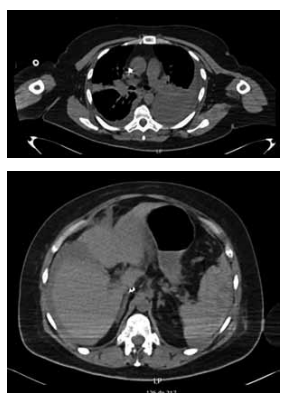

Mulher de 65 anos, com necessidade de toracocentese

de alívio por extenso derrame pleural à esquerda, que

causava dispneia. Realizada punção no 8o

espaço intercostal, linha axilar média, com saída de 20 mL de líquido serossanguinolento, sem saída adicional de líquidos.

Trinta minutos após o procedimento, a paciente evolui

descorada, com frequência cardíaca de 100 bpm e PA

de 85 x 60 mmHg, queixando-se de dispneia e dor abdominal. Realizou a tomografia demonstrada nas imagens

a seguir: